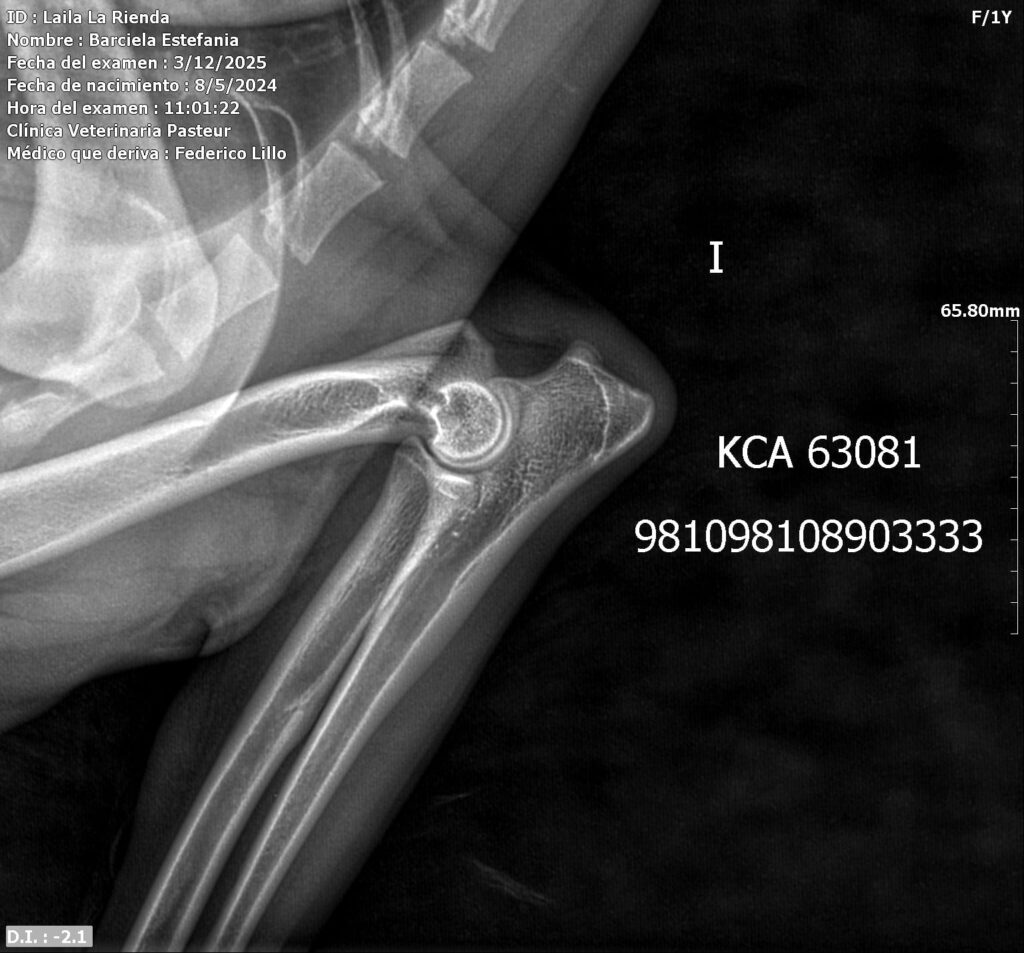

Placas de caderas y codos en La Rienda Border Collie

En La Rienda Border Collie la cría responsable no es un eslogan: es una forma de trabajar desde hace años. Por eso, nuestros machos reproductores y algunas de nuestras hembras cuentan con estudios radiológicos de caderas y codos, un paso clave para garantizar cachorros sanos, equilibrados y con una excelente calidad de vida.

Realizamos radiografías oficiales de caderas y codos a nuestros reproductores, evaluadas por profesionales veterinarios especializados.

Estos estudios permiten detectar posibles patologías hereditarias, como la displasia de cadera y de codo, ayudando a reducir su incidencia generación tras generación.

✔ Clasificación A en caderas y codos, indicativo de articulaciones sanas y excelente conformación

✔ Clasificación A en codos y B en caderas, siempre informada con total transparencia y criterio de selección responsable

Seguiremos incorporando estudios de caderas y codos a medida que nuestros perros alcanzan la edad correspondiente, reafirmando nuestro camino de crianza seria, transparente y basada en evidencia veterinaria.